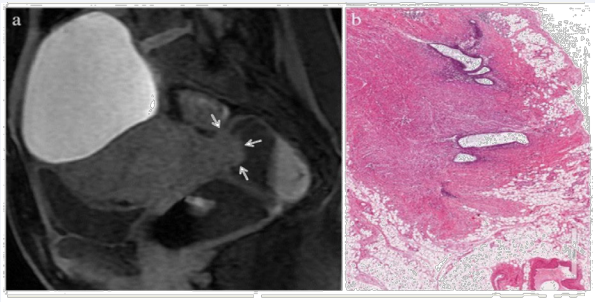

Although not a particularly useful screening tool specialist trans-vaginal ultra-sound and magnetic resonance screening (MRI) are important tools to further stage the disease so that an appropriate care plan can be developed. It is important to establish whether the vaginal mucosa is involved and crucially whether there is involvement of the rectal muscularis, typically at the recto-sigmoid junction as the rectum leaves the peritoneal cavity. The signs are however subtle and need to be assessed in expert centres with appropriate expertise as they are easily missed.